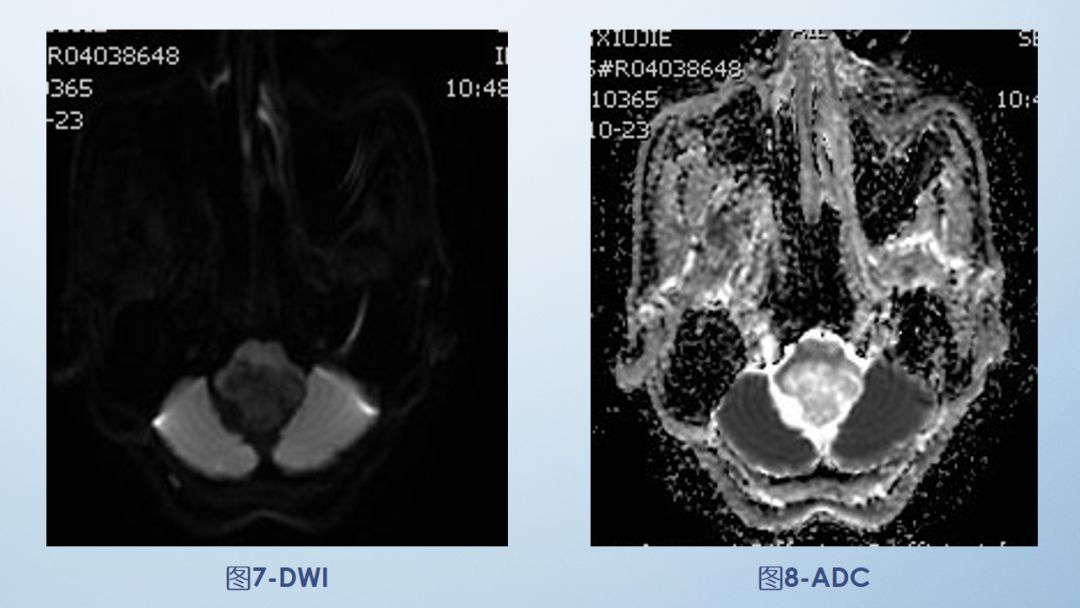

影像描述:小脑延髓池内见不规则异常信号影,呈等及稍长T1长T2信号,内部信号不均,边缘见稍粗大流空信号血管影,FLAIR病灶中心少许片状低信号,增强呈明显强化,DWI不均低信号,ADC不均高信号。小脑半球、延髓、第四脑室受压变形。临近延髓受压变窄,呈长T1长T2信号。

·肿瘤多类圆形,60%囊实混合性,大囊小结节,增强囊性部分无强化,囊壁若为肿瘤细胞可有环形强化,40%实性,周围可有水肿,增强明显强化,肿瘤周围及内可见血管流空信号影为典型特征。DWI为低信号。